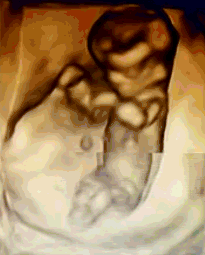

什么是NT检查

NT是胎儿颈部半透明膜的缩写,是10~13孕周围绕在胎儿颈项后部流动性的半透明蛋白膜。它的厚度与胎儿DS缺陷正相关,并可以通过超声成像测量。

NT排畸检查是指胎儿颈后部皮下组织内液集聚的厚度的检查。通过B超测定颈项透明层厚度,便于及早发现唐氏儿和先天性心脏病的胎儿,并及时予以干预。